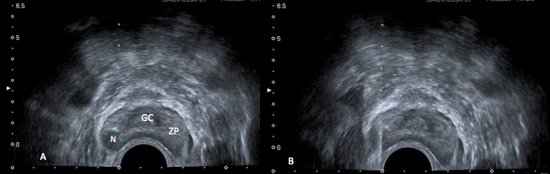

Cerca de 60 – 70% dos tumores da zona periférica são hipoecogênicos em relação ao restante da próstata (fig. 1), entretanto apenas 17 – 57% dos focos hipoecogênicos representam câncer. Causas benignas como atrofia ou prostatite se apresentam de forma semelhante no ultrassom transretal. Além disso, 30 a 40% dos tumores são isoecogênicos, indistinguíveis do parênquima prostático normal. A USTR em pacientes sem alterações ao toque retal apresenta sensibilidade de apenas 30-45%.7,8

Figura 1. A) Ultrassonografia transretal da próstata demonstrando a anatomia prostática: glândula central (GC) discretamente hipoecogênica, e a zona periférica (ZP), mais ecogênica. Nota-se nódulo (N) bem delimitado, hipoecogênico, na zona periférica. B) Biópsia transretal da próstata.